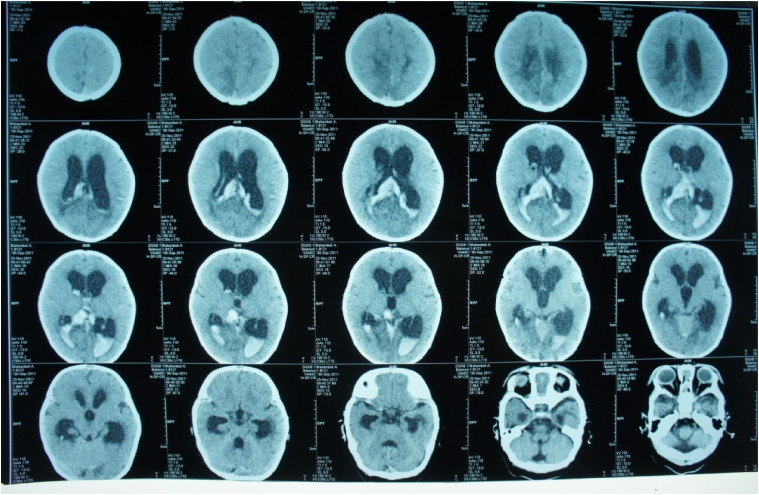

Abstract Image